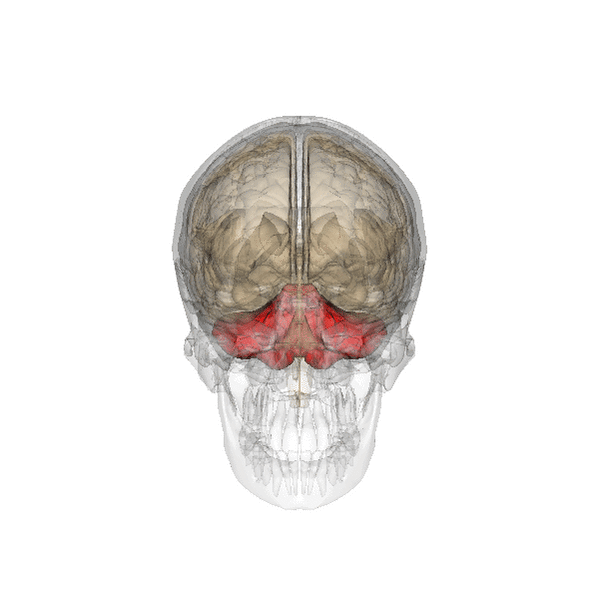

Анатомия мозжечка человека

Особенностью мозжечка человека является то, что он, так же как и головной мозг, состоит из правого и левого полушарий (лат. hemispheria cerebelli) и соединяющей их непарной структуры — «червя» (лат. vermis cerebelli). Мозжечок занимает почти всю заднюю черепную ямку. Поперечник мозжечка (9-10 см) значительно больше его переднезаднего размера (3-4 см)[19].